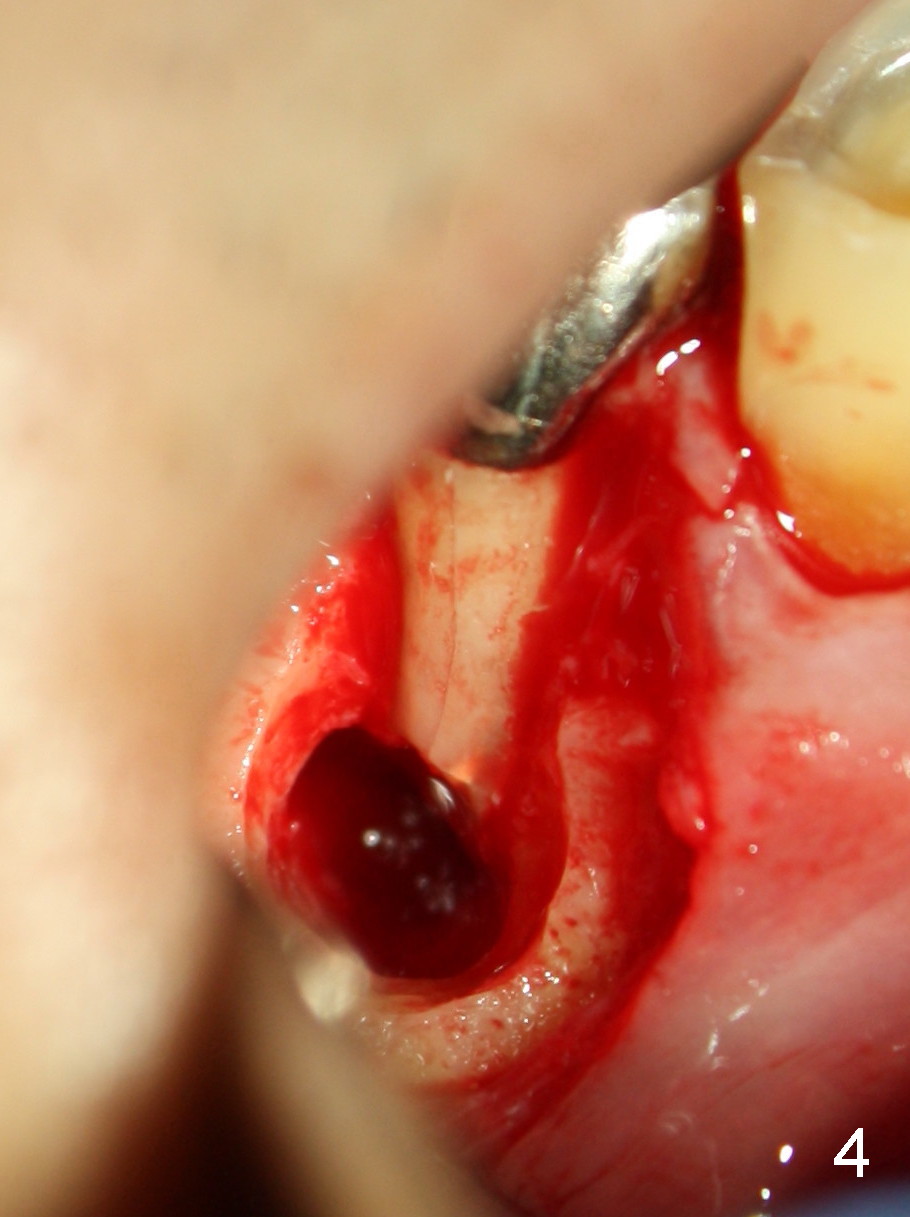

一般来说根切最难处在于翻瓣后寻找根尖病变,为什么这次不劳而获呢?整个近中根暴露在光天化日之下?当时思路不敏捷,眼光狭窄,为表面现象沾沾自喜(骨质变化(根尖周围以及根分叉(图一箭头)),忙于清除那里肉芽组织(包括之前除去根尖周围骨质),突然把注意力转移到近中根,发现本人意料不到情况(不过事先Dr.

Peter Tian要求排除这个情况),使用双氧水冲洗伤口以及近中根,拍摄聚焦于近中根病变(图四),马上给病人看,向他解释这种病变可能是根管治疗原因(图三),而不是根管治疗所致,拼命摔掉背着黑锅,他回答却是“真的吗?”

Dear Dr. Jin: In fact, I am

trying to play a trick to test whether our readers are good at detecting

abormality from photos or from real patients or not. There is a vertical crack

involving the mesial root buccally (Fig.4, in which no label is used to indicate

the crack). At least the mesial root is hopeless, not to mention bone graft. The

most conservative treatment is hemisection or root amputation, but the patient

did not want to do anything right now. I plan to place implant at the site of

#31 while the infection at #30 is not so severe after apicoetomy. Once the

implant at #31 proves to work, I will persuade the patient to extract and

implant #30.